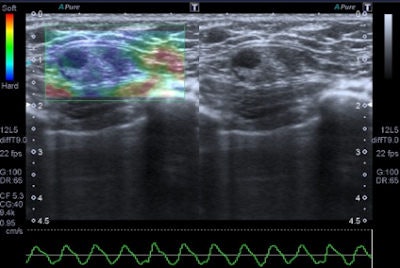

Freehand ultrasound, or compression elastography ("strain elastography"), is based on the application of a compressive force to the breast and on the measurement of the shape-deforming effect, thus providing a value of lesion stiffness compared with that of surrounding tissues, the authors wrote. A slight manual compression/decompression is applied using a conventional transducer, or the deformation may be determined by respiratory movements.

"The technique allows only for qualitative and semiquantitative assessments of a lesion because the force exerted by manual compression is unknown to the equipment, thus allowing only the calculation of the deformability ratio (strain ratio) and not the absolute elasticity," Ricci wrote and colleagues.

Benign lesions are described at elastography as lesions with a low color map score (score 1-2), while the best cut-off point for discriminating benign from malignant masses falling at the 3-4 boundary of color map classification, according to the Ueno-Itoh score system. Cysts often appear as hard and low deformable lesions, commonly represented with a blue pattern at the color map and with a high strain ratio because of their low compressibility.

Editor's note: In the image on our home page, the shape and infiltration of the breast tumor is demonstrated in 4D Hitachi real-time tissue elastography (HI-RTE). Image courtesy of Hitachi Aloka, previously published in the ECR Today newspaper.